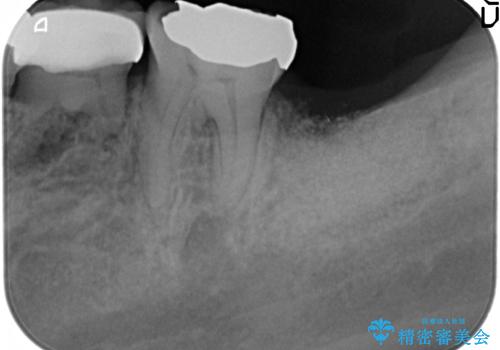

最後方臼歯周囲には大きな透過像が見られ、破折が強く疑われること抜歯が想定されることを理解していただき銀歯を除去したところ破折が認められたため抜歯を行いました。

良好なインプラントの植立を行うためには、十分な骨量があることが必須条件です。

術前、歯の破折により大きな骨の吸収が認められていたため骨量を十分に回復するために抜歯と同時に歯槽堤保存術を行い十分な骨量の回復をすることができました。